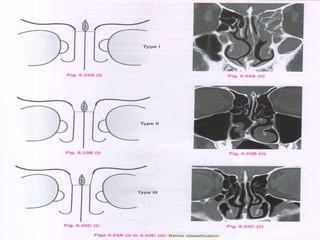

 I –Type I frontal cell (a single air cell above agger

nasi)

 II –Type II frontal cell (a series of air cells above

agger nasi but below the orbital roof)

 III –Type III frontal cell (this cell extends into the

frontal sinus but is contiguous with agger nasi )

 IV –Type IV frontal cell lies completely within

the frontal sinus (Loner cell)

TYPES OF FRONTAL CELLS-

KEROS CLASSIFICATION-

 The Keros classification is a method of classifying the

depth of the olfactory fossa.

 In adults, the olfactory recess is a variable depression in

the cribriform plate that medially is bounded by the

perpendicular plate and laterally by the lateral lamella. It

contains olfactory nerves and a small artery

 The depth of the olfactory fossa is determined by the

height of the lateral lamella of the cribriform plate. Keros

in 19621, classified the depth into three categories.

 type 1 : has a depth of 1 - 3 mm (26.3% of population)

 type 2 : has a depth of 4 - 7mm (73.3% of population)

 type 3 : has a depth of 8 - 16mm (0.5% of population)